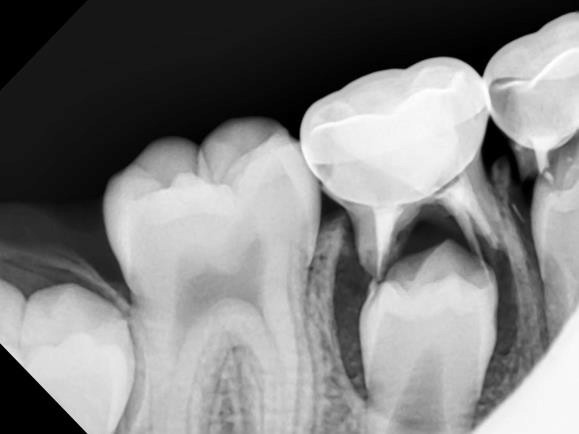

A new paper in Science Advances describes for the first time how minerals come together at the molecular level to form bones and other hard tissues, like teeth and enamel.

The University of Illinois Chicago researchers who published the paper described their experiments -- which captured high-resolution, real-time images of the mineralization process in an artificial saliva model -- and their discovery of distinct pathways that support bone and teeth formation, or biomineralization.

Shahbazian-Yasser and his colleagues observed that both direct and indirect formations of hydroxyapatite crystals -- the foundation of hard tissues -- can be achieved by local variations in energetic pathways for nucleation and growth.

"The control over the dissolution of amorphous calcium phosphate affects the assembly of hydroxyapatite crystals into larger aggregates," Shahbazian-Yasser said. "Using technology developed at UIC, we found evidence that these pathways coexist simultaneously -- explaining why different groups had reported seemingly different or opposite results. In addition, we now understood how hydroxyapatite materials nucleate and grow on amorphous calcium phosphate templates. The control over the nucleation and growth of hydroxyapatite will aid in developing new drugs and medical treatments to heal lost or broken bone faster or cure tooth cavities."

To capture the images, the researchers used a unique micro-device that made it possible to use electron microscopy with a liquid model. Using this method, the researchers were able to monitor chemical reactions in the model on the smallest scale.

"Our study provides clear, new evidence of how minerals organize and grow into bone materials, and this finding has many important implications for further research on bone or teeth healing," Shahbazian-Yasser said.